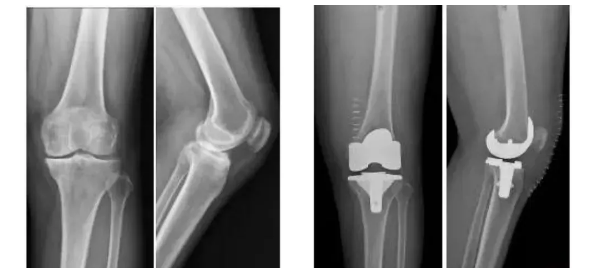

3D打印生物型人工膝關節在國內成功植入!

膝關節骨關節炎是一種退行性疾病,近年隨著經濟發展和人口老齡化趨勢日趨明顯,尤其是在中老年群體發病率較高,因此膝關節置換術需求量日益增長。此外,隨著居民生活水平的提高,大多患者對于膝關節置換術術后的生活質量和植入假體有了更高的要求,隨之假體在設計和創新方面也更精準、更便捷化。全球shou款3D打印分區骨小梁生物型膝關節假體正是在這種高需求與高期待的新形勢下應運而生。

目前臨床上使用的膝關節假體多為骨水泥固定型假體,骨水泥即骨粘固劑,它可以將膝關節假體固定在骨界面上。骨水泥固定存在一定局限,如骨水泥單體具有一定的毒性;與骨接觸面的骨溶解問題;隨著時間推移,會發生變形和退變等。

本次植入的生物型膝關節假體在術中無需使用骨水泥,通過機械方式進行固定,即假體與骨組織的緊密結合,獲得假體的初始穩定性,遠期骨組織長入假體表面的微孔內部,實現由機械固定向生物.內鎖固定的轉化,zui終經過骨整合作用獲得良好固定,預期能夠獲得更長的假體壽命。此外,生物型膝關節假體避兔了骨水泥相關并發癥的發生,縮短了手術時間,zui大程度保留了骨組織。因而減輕了患者術后疼痛,降低了圍術期并發癥發生率,有利于患者術后快速康復。

周宗科教授介紹說,該款3D打印分區骨小梁生物型膝關節假體有三個亮點,一是脛骨平臺假體采用了3D打印骨小梁分區技術,三分區設計使宿主骨均勻骨長入,避免因應力分布不均而造成平臺假體松動等問題;二是所用股骨髁假體表面為真空等離子噴涂純鈦涂層,其粗糙的接觸面增加了骨誘導的能力,具有優異的即刻穩定和長期穩定性;三是所用平臺墊為添加維生素E的高交聯超高分子量聚乙烯材質,具有優異的耐磨性能。